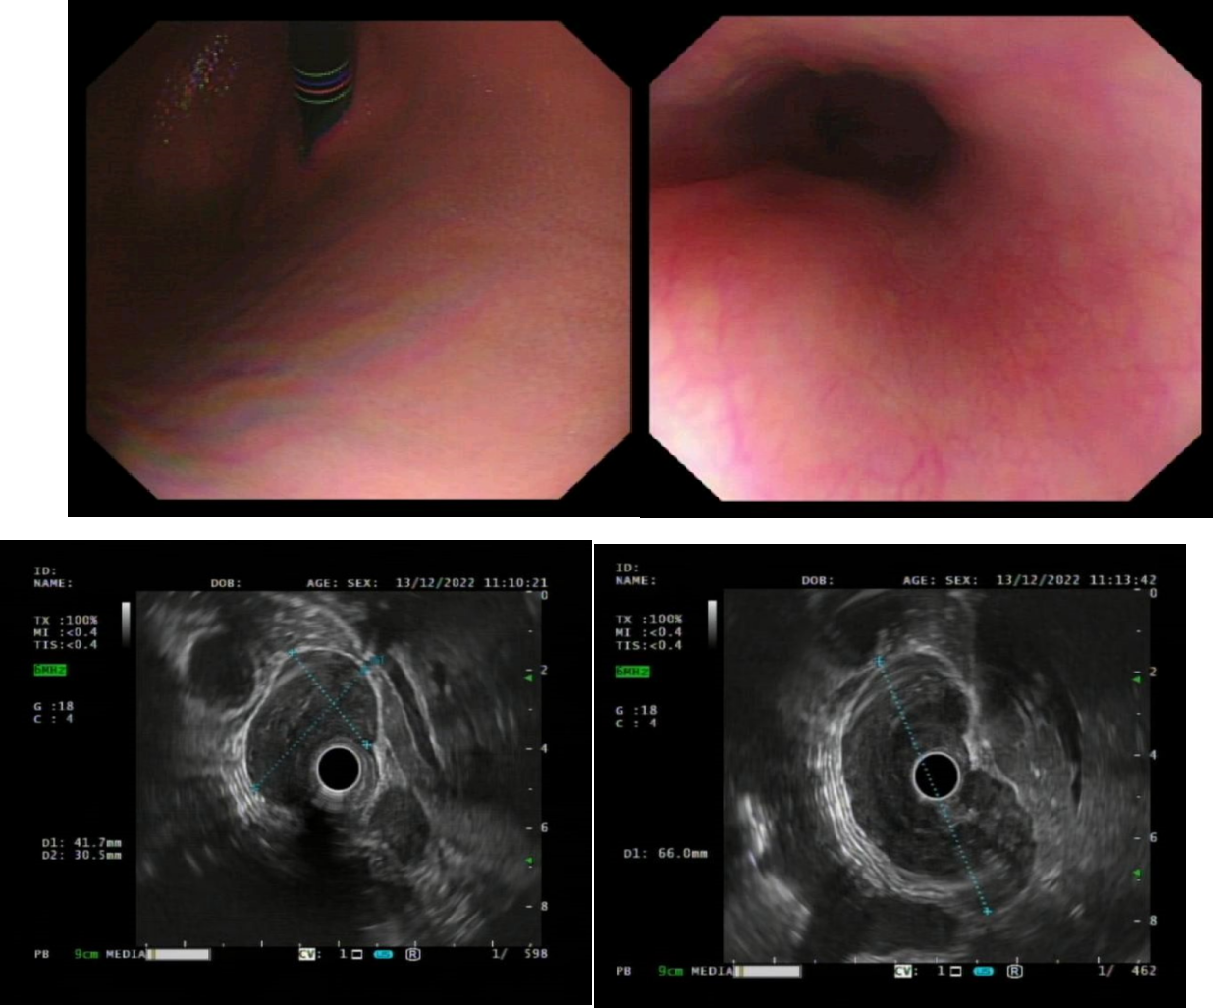

The patient, a 30-year-old female visited hospital with belching and difficulty swallowing symptoms and sought medical attention in Changzhou No.2 People’s Hospital. An enhanced chest CT scan indicated significant thickening of the lower esophageal wall near the cardia, with the thickest part measuring approximately 2.5 cm, showing mild enhancement in CT examination.

The endoscopic ultrasound showed a submucosal tumorin the lower segment of the esophagus, with a smooth surface and a ring-shaped tumor at the cardia. A hypoechoic mass is located at 37-43 cm from the incisors, with uneven internal echoes, pressing against the esophageal wall and having indistinct boundaries with the esophageal wall, measuring 5.8*3.7 cm in section.

The 3D reconstruction indicates that a large tumor encircles the esophagus and it is adjacent to the aorta. The tumor has a "hoof-shaped" around the junction of the esophagus and the cardia, with the major axis measuring approximately 6.4 cm and the minor axis measuring approximately 3.7 cm.